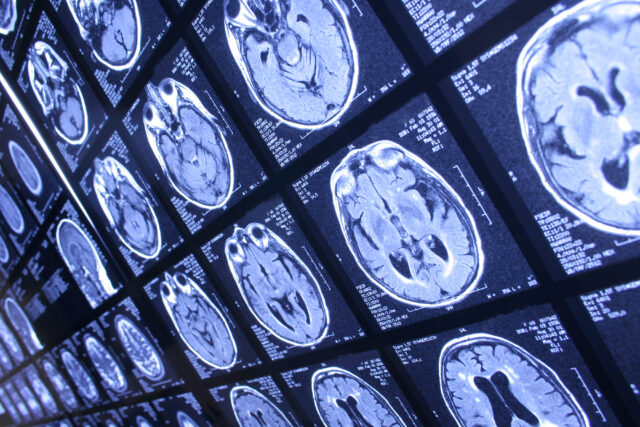

El equipo de Ciencia e ingeniería del Child Mind Institute se dedica a transformar la vida de los niños con trastornos mentales y del aprendizaje a través del poder de los descubrimientos científicos. Para abordar la creciente crisis en la salud mental infantil, nuestros investigadores trabajan para guiar las intervenciones mediante una comprensión rigurosa del cerebro en desarrollo, comprensión que se basa en resultados científicos reproducibles, en lugar de teorías o evidencia anecdótica.

Uno de los mayores obstáculos para mejorar las intervenciones en salud mental de manera confiable es el hecho de que tanto el diagnóstico como el tratamiento son subjetivos. Estamos liderando un esfuerzo global dirigido a identificar biomarcadores cerebrales y conductuales objetivos y medibles que guíen la práctica clínica.

Hay una crisis de reproducibilidad en psicología. Por esto, en el Child Mind Institute nos centramos en mejorar los métodos en la investigación del cerebro. Estamos desarrollando herramientas de análisis y de neuroimagen que permiten a los científicos agrupar los datos, obtener una visión más profunda de las señales cerebrales y fortalecer la ciencia que sustenta los tratamientos de salud mental.